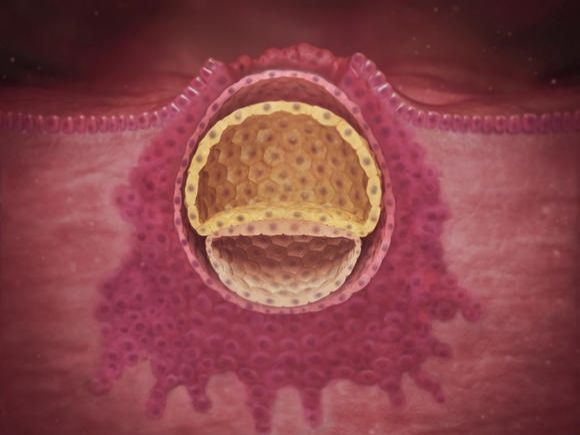

3. týden těhotenství

Maminka

Během tohoto týdne došlo k oplodnění vajíčka spermií a to se po několika dnech od početí uhnízdilo v pelíšku, který pro něj...